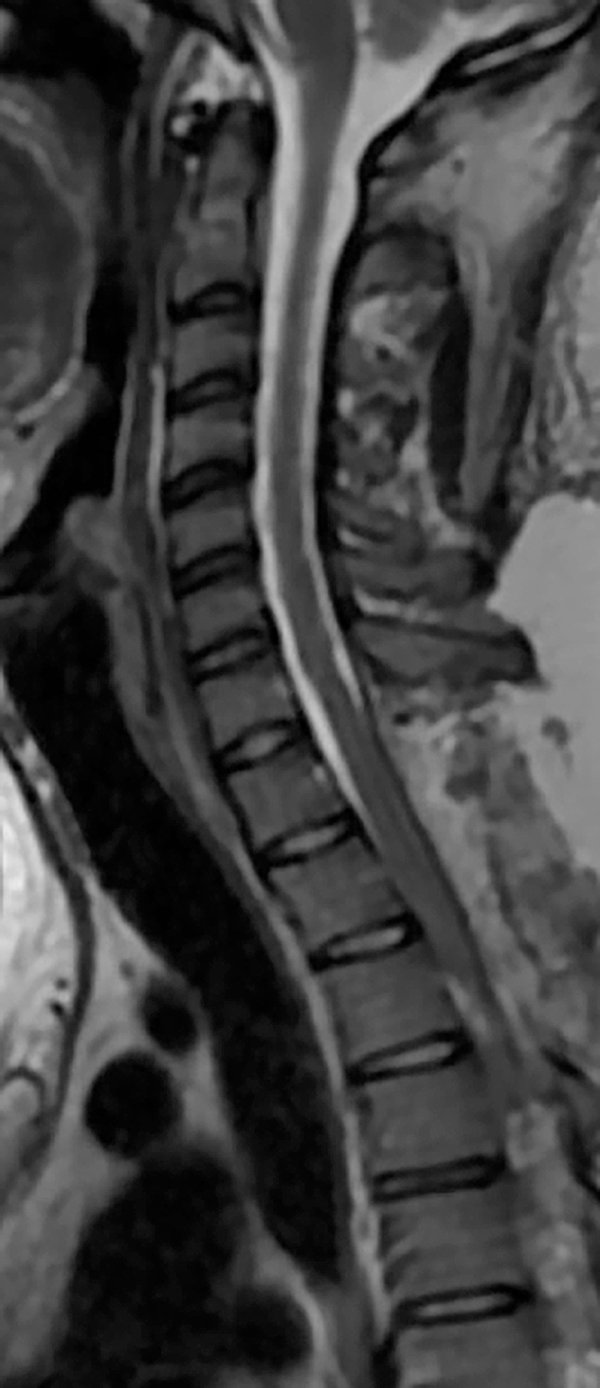

Se presenta el caso de una paciente de 21 años de edad, con antecedentes de infección por VIH, sífilis, consumo de drogas ilícitas y alcohol, que consulta por parestesias en ambos miembros inferiores de 6 meses de evolución, a lo que agrega paraparesia y dificultad en la marcha en los últimos 3 meses, con empeoramiento progresivo. Al examen físico presentaba una paraparesia moderada, hipertonía, hiperreflexia e hipoestesia en todas las modalidades sensitivas en miembros inferiores con nivel sensitivo T4 y signo de Babinski bilateral, así como también dolor dorsal con irradiación a ambos miembros inferiores. En la resonancia magnética (RMN) de columna completa se observaba una imagen a nivel T1 a T3, hipointensa en T1, hiperintensa en T2 y STIR, sin captación de contraste endovenoso, con desplazamiento posterior de la médula espinal y adelgazamiento de la misma (Figura 1 y 2). Se interpretó el cuadro como un quiste aracnoidal asociado a una aracnoiditis adhesiva. En este contexto, debido a la progresión y severidad de los síntomas, se realizó laminotomía T1-T2-T3 y evacuación de la lesión quística en el mismo nivel (Figura 3). Se enviaron muestras de aracnoides a anatomía patológica, la cual demostró “fragmento de tejido dural con fibroesclerosis y vasocongestión”; a su vez se realizaron cultivos de gérmenes comunes, hongos, parásitos, tuberculosis y PCRs virales, los cuales resultaron negativos.

Figura 1: Resonancia magnética de la paciente, se observa lesión quística a nivel T1-T2-T3, con desplazamiento posterior de la médula espinal y adelgazamiento de la misma. A- En secuencia T1 se visualiza la lesión quística hipointensa; B- En secuencia T2, la lesión quística es hiperintensa; C- En STIR la lesión quística también es hiperintensa, correlacionándose con la señal del LCR.

Figura 2: RMN con corte sagital (A) y axiales a distintos niveles (B). Se observa el desplazamiento posterior de la médula espinal y el quiste anterior a la misma.